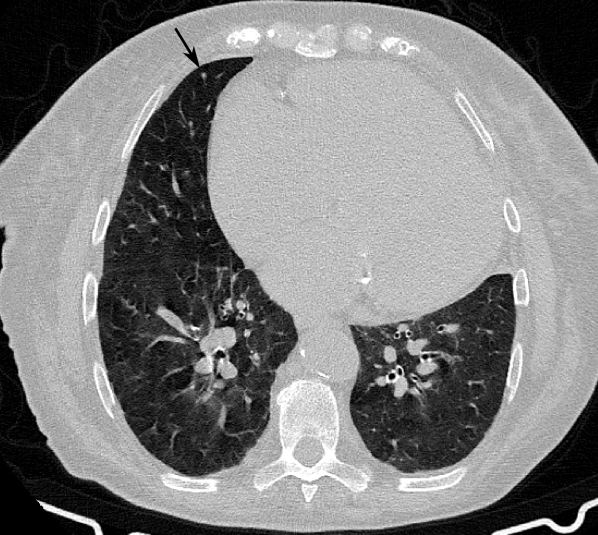

Figure 3 shows the detection performance of CAD and each radiologist when considering the remaining radiologists as ground truth for each agreement level. Within the same agreement level, the average radiologist has a higher sensitivity than the CAD with 0.85 and 0.88 FPs per scan for agreement levels 1 and 2, respectively. The CAD system is able to obtain the same sensitivity as the average radiologist only at 5.99 and 5.80 FPs per scan for agreement level 1 and 2, respectively. Figure 4 shows examples of nodule candidates proposed by the automatic detection.

Refer to caption

Figure 4: Central axial view (51×\times51mm) of CAD detection examples on CTs annotated by 3 radiologists. Lines correspond to detection candidates with the same agreement level (findings annotated by 3, 2, 1 and 0 radiologists from top to bottom). Columns correspond to candidates with similar probability as given by the FP reduction algorithm (lower right corner of each frame). The seven probability levels correspond to a FP/scan level of 1/8, 1/4, 1/2, 1, 2, 4 and 8 for nodules with agreement level 2 (right to left).